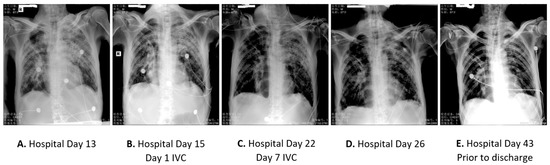

2.2. Case 2